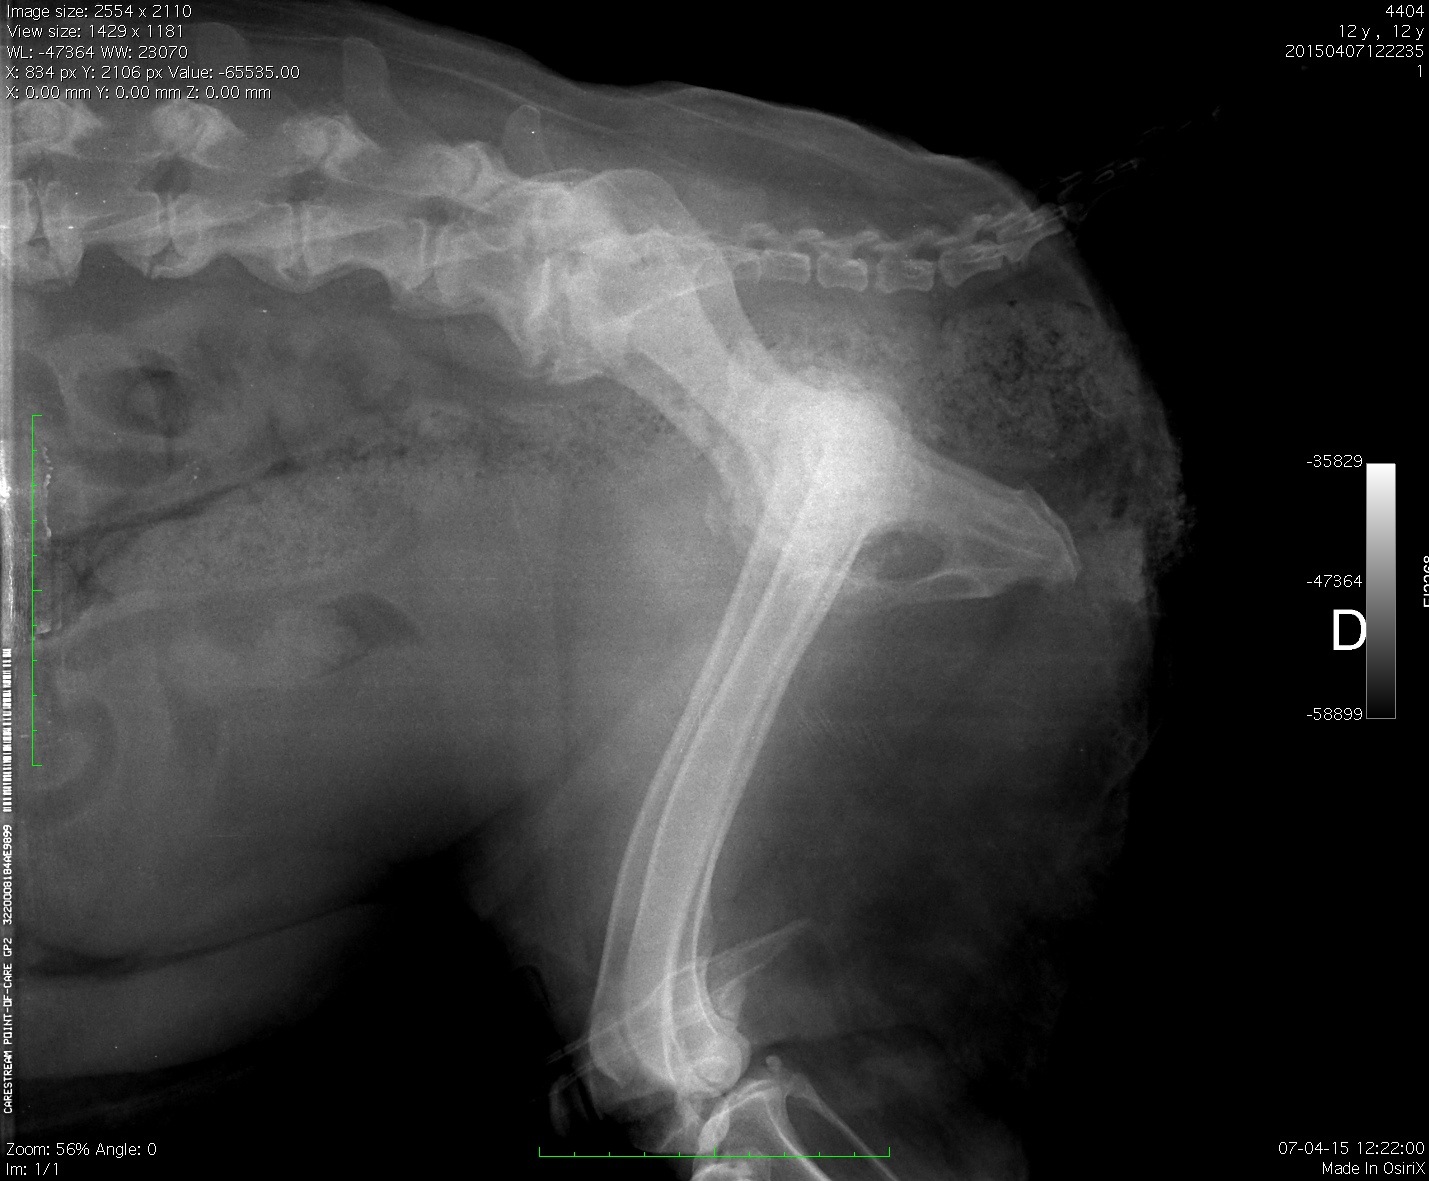

Paciente canino, 12 años, dolor agudo coxofemoral combinado con agresividad a la manipulación

Se adjuntan proyecciones L-L y V-D de columna lumbosacra, pelvis y abdomen caudal.

Respecto a los radiodiagnósticos, podemos afinar que el paciente cursa con:

I. Displasia de cadera

II. Inestabilidad lumbosacra

III. Proceso agresivo coxofemoral

IV. Vértebra transicional